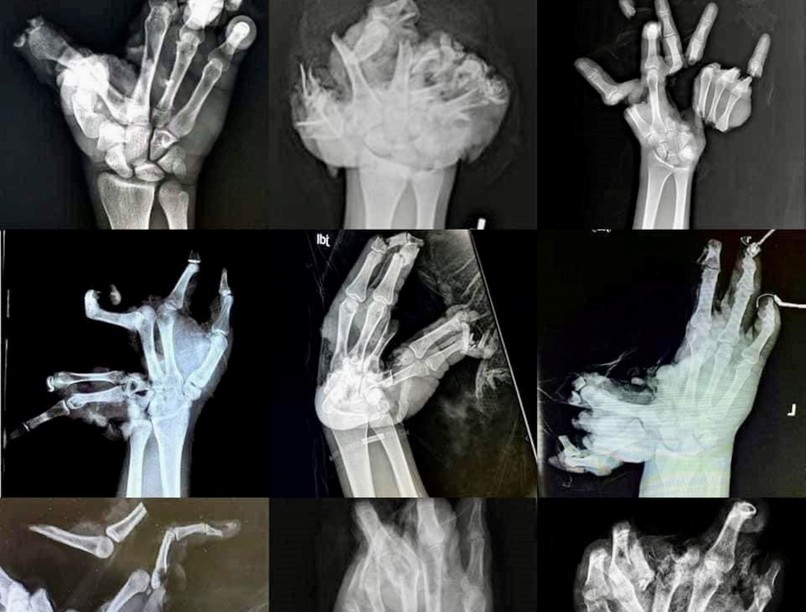

Leszakadt ujjak, szétroncsolódott kézfejek

A mentők közösségi oldalán korábban közzétettek egy elrettentő montázst: az összeállításban kilenc rémisztő röntgenképet láthatunk petárdarobbanásban megsebesült kézfejekről, leszakadt ujjakról, szétroncsolódott végtagokról.

Kilenc indok, hogy miért ne vegyen petárdát